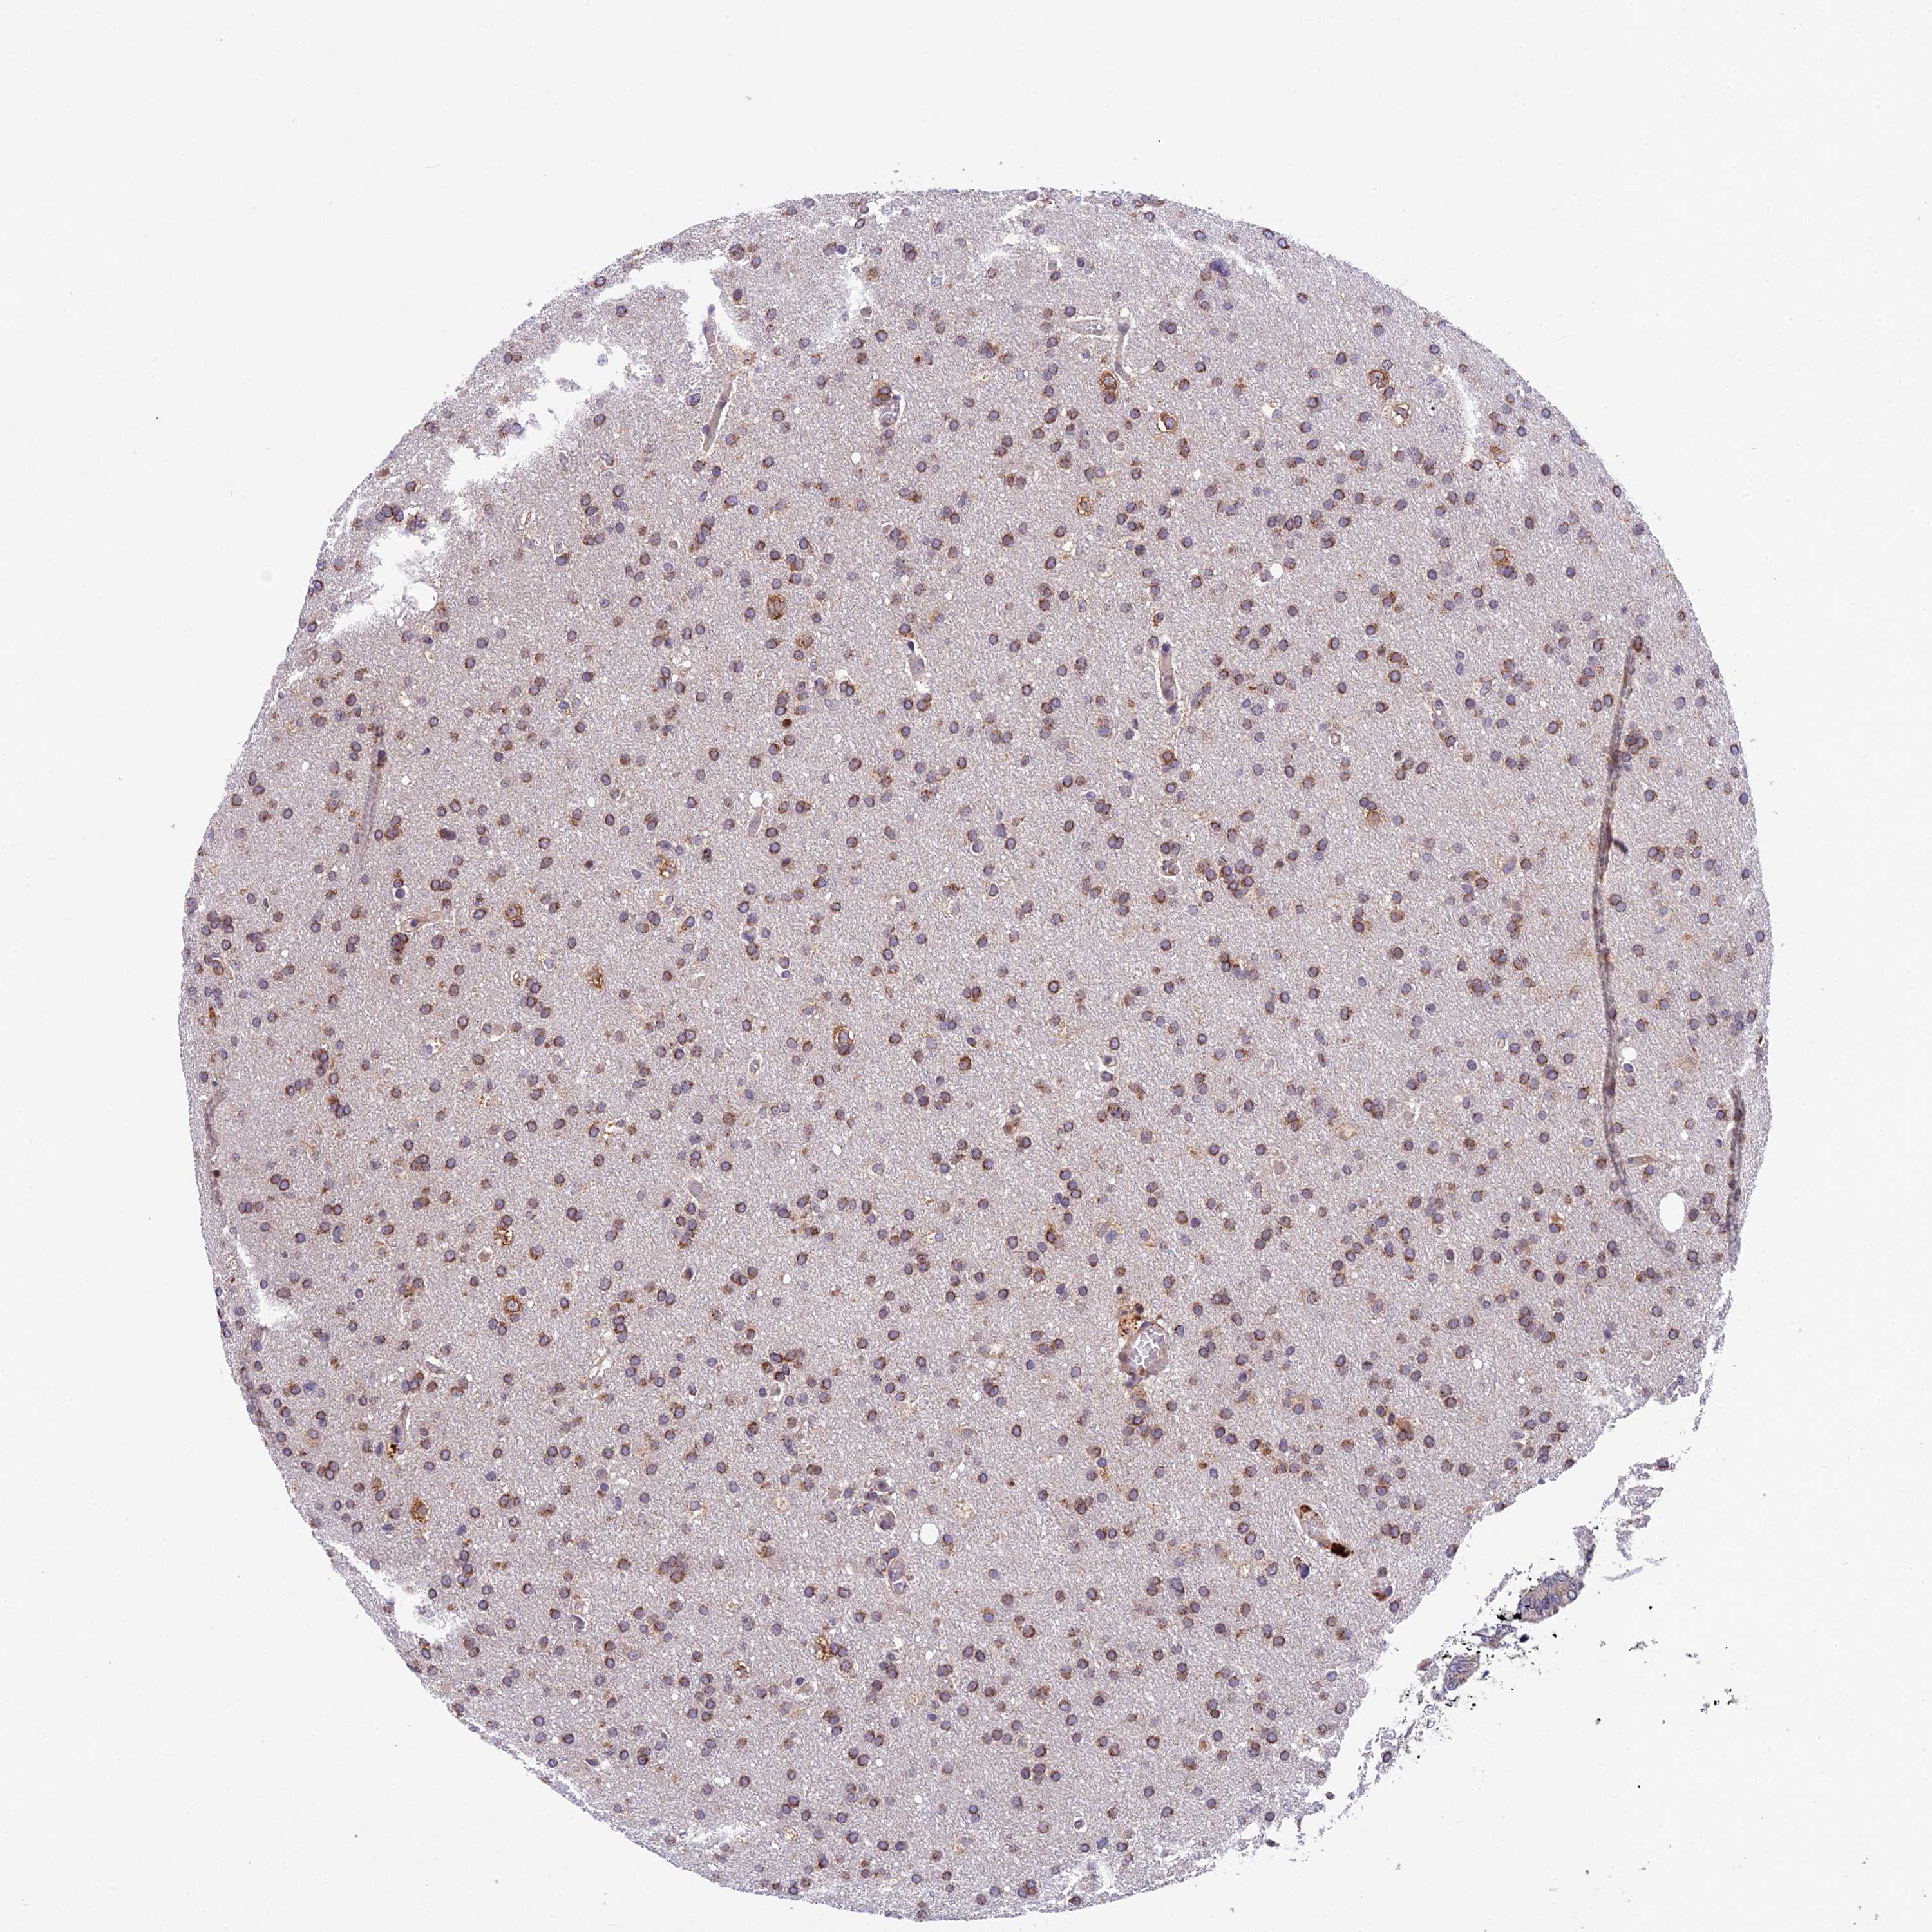

GLIOMA - Protein expressioni

A mouse-over function shows sample information and annotation data. Click on an image to view it in a full screen mode. Samples can be filtered based on level of antibody staining by selecting one or several of the following categories: high, medium, low and not detected. The assay and annotation is described here.

Note that samples used for immunohistochemistry by the Human Protein Atlas do not correspond to samples in the TCGA dataset.

Antibody stainingi

Antibody staining in the annotated cell types in the current human tissue is reported as not detected, low, medium, or high, based on conventional immunohistochemistry profiling in selected tissues. This score is based on the combination of the staining intensity and fraction of stained cells.

Each image is clickable and will lead to virtual microscopy that enables deeper exploration of all samples and also displays staining intensity scores, fraction scores and subcellular localization as well as patient and tissue information for each sample.

Antibody HPA041880

Antibody HPA054709

Glioma, malignant, High grade

Glioma, malignant, Low grade